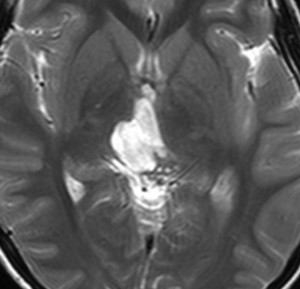

MRIです

左の拡散強調画像で高信号となり類表皮のう胞 epidermoid cyst あるいは類皮のう胞 dermoid cyst の診断です。しかし右のT2強調画像では左後方に違う信号の腫瘍塊があります。

ガドリニウム増強像です。類皮のう胞(成熟奇形腫 mature teratoma)との混合性胚細胞腫瘍を強く疑う所見です。